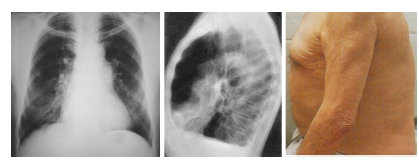

O enfisema é uma doença caracterizada pelo excesso de ar na região pulmonar, estado que é consequência de um complexo processo obstrutivo e destrutivo dos alvéolos e dos bronquíolos terminais (ácino pulmonar) que acarreta a perda da elasticidade pulmonar. Nos alvéolos, ocorre uma hiperdistensão com dilatação excessiva, o que gera uma ruptura dos septos alveolares. A distribuição e a abrangência da lesão variam em cada caso. A seguinte imagem radiológica é típica de paciente enfisematoso.